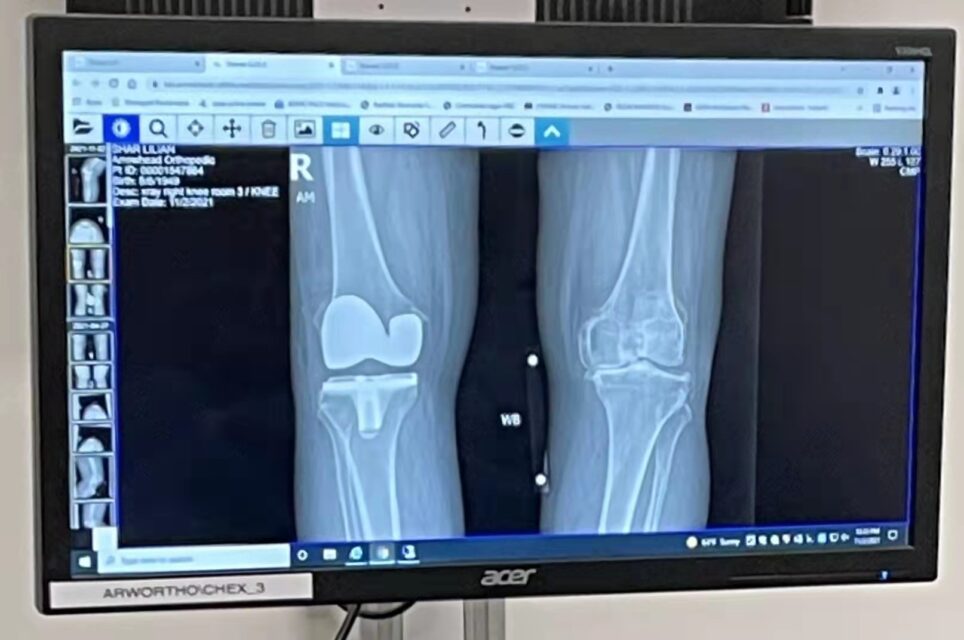

由於膝關節越來越疼痛,所以 夫君煜群和二弟志文陪同我到醫院,還是請那位曾經給媽媽置換 過膝關節的印度醫生幫我置換膝關節,醫生要我先照膝關節X光,之後,醫生告訴我,我的膝關節因各種原因發生磨損、軟骨己被侵蝕掉了,還有骨刺,

半月板和膝關节韌帶都損傷。 導致關節間隙狹窄,膝關節疾病通常會導致關節部位出現腫脹和疼痛,行走疼痛及功能障礙,並且伴隨着活動限制,下蹲也非常困難。,嚴重影响生活質量。

左右膝關節的對比

主治醫師查看我的膝關節X光片